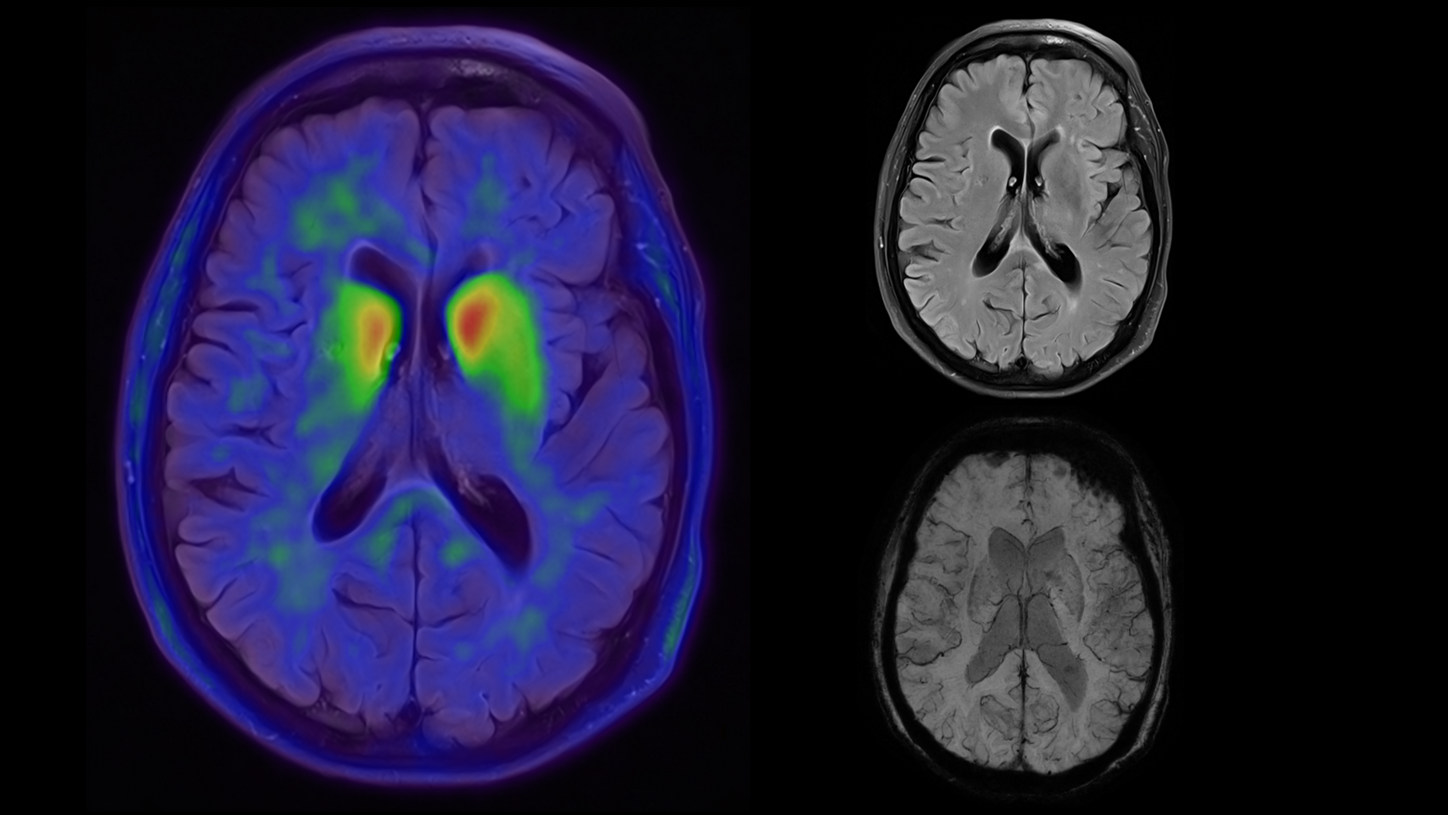

BIOGRAPH One excels in PET/MR precision to support confident diagnostic decisions. Featuring the Optiso UDR Pro detector with the largest 35 cm axial FOV2 and the best time resoulution2 in PET/MR, it enables comprehensive capture with excellent sensitivity and ultra-fast TOF3 in real time 鈥 delivering exceptionally clear, detailed images even in low-dose settings.

With Deep Resolve for accelerated acquisition and improved resolution in 2D and 3D applications4, BIOGRAPH One makes PET/MR exams faster than ever before. With an exceptional 3T magnet at its heart, BIOGRAPH One delivers unparalleled performance with outstanding homogeneity, a large 55 x 55 x 50 cm鲁 field of view and robust gradient power.